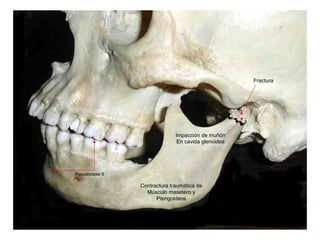

Un porcentaje muy alto e las disgnatias se deben a traumas recibidos directa o indirectamente

En la articulación, de la misma manera sucede con los casos de crecimiento asimétrico de los

Cóndilos.

Cóndilo fracturado

Músculo pterigoideo externo contracturado

Apófisis ptrigoides

El desplazamiento condilar y su proceso inflamatorio,

Pueden hacer compresión sobre los elementos que atraviesan

Los agujeros redondo mayor, menor y rasgado.

Intrusión dentaria a las 72 horas del trauma

Area decontactos prematuros en las

Primeras 72 horas y de intrusión dentarias

En el tiempo subsiguiente.

Falta de contacto

dentario inicial.

Posteriormente

Supraerupción.

Inicio de laterognatia y posteriormente hipoplasia mandibular izquierda

Un porcentaje muyalto e las disgnatias se deben a traumas recibidos directa o indirectamente En la articulación, de la misma manera sucede con los casos de crecimiento asimétrico de los Cóndilos.

Cóndilo fracturado Músculo pterigoideoexterno contracturado Apófisis ptrigoides El desplazamiento condilar y su proceso inflamatorio, Pueden hacer compresión sobre los elementos que atraviesan Los agujeros redondo mayor, menor y rasgado. Intrusión dentaria a las 72 horas del trauma

Area decontactos prematurosen las Primeras 72 horas y de intrusión dentarias En el tiempo subsiguiente. Falta de contacto dentario inicial. Posteriormente Supraerupción. Inicio de laterognatia y posteriormente hipoplasia mandibular izquierda